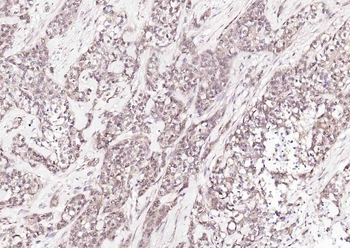

50 μl, 100 μl - Featured

ICC, IF, IHC-Fr, IHC-P, WB

Human, Mouse, Rat

Zebrafish

Rabbit

Recombinant

Unconjugated

50 μl, 100 μl, 25 μl - Anti-KIFC1 Antibody [orb865535]